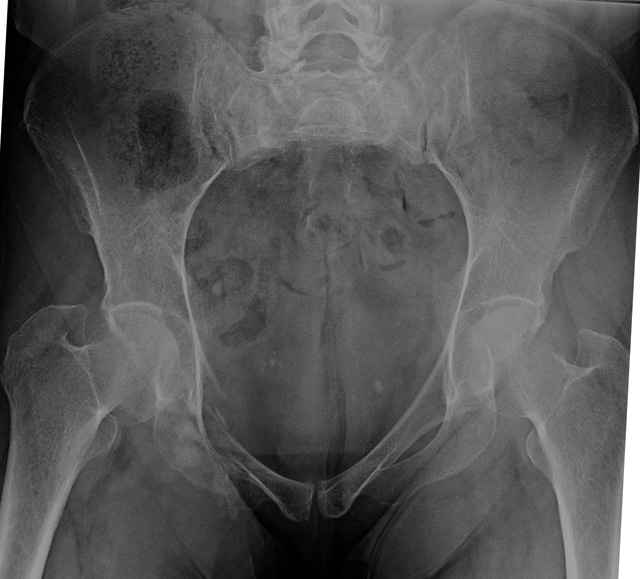

Here are a recent patient’s example slides...

54 yo Female Fell c/o Pain

3 Months After Fall

Continued Pain & Immobility

(+) Instability to Compressive Manual Exam

Pelvic CT Scan - 3 Months After Fall

Sacral Injuries

Ramus Fractures

Percutaneous Fixation

(B) Ramus-Retrograde

2 TransIliac-TransSacral

Upper Segment